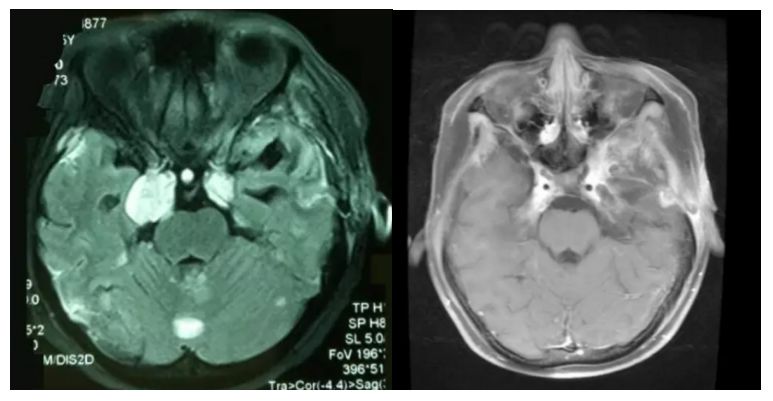

质子治疗前MR图像(左):可见颅内多个占位病变

质子治疗一个月后MRI复查图像(右):肿瘤明显缩小,头痛头晕、走路不稳症状明显改善